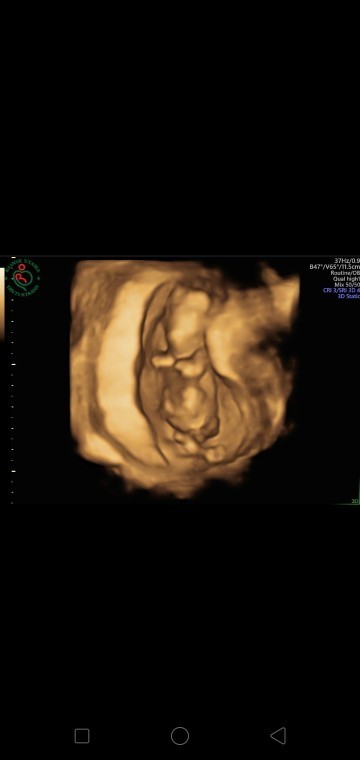

Halo bunda semua..aku masih rada takut nih dikandungan yg sekarang karna pernah mengalami hal pait yaitu bayi meninggal 8 bulan kandungan.. jd kalo mau minum susu hamil seperti Prenagen gitu harus resep/persetujuan dokter apa bebas aja ya Bun?? Soalnya aku ga tau dan bingung#Nanya #bantusharing